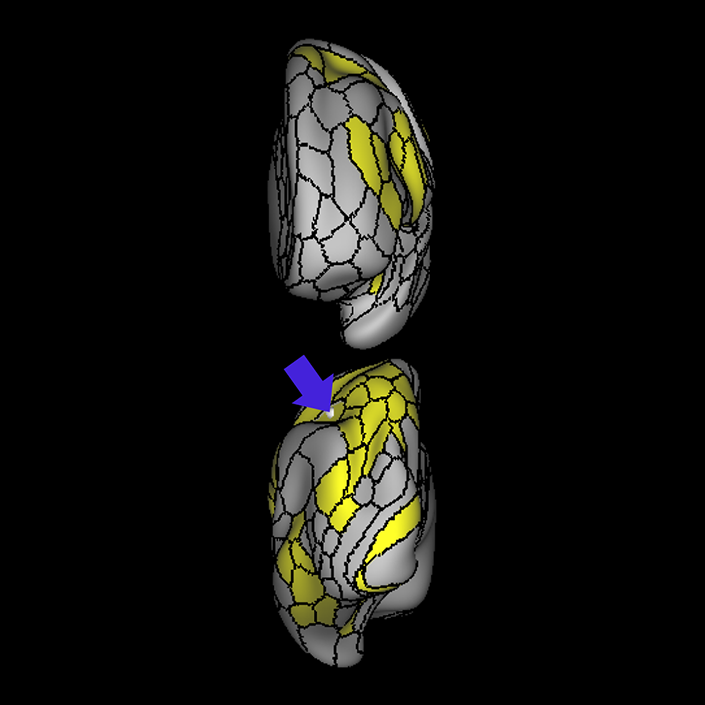

ᐅ SummaryArea 44: part of the inferior frontal gyrus of the lateral frontal lobe. Translates abstract and intentional information in the prefrontal cortex to more detailed representations to help guide the production of verbal and manual actions. In addition to its known association with Broca's area, is sometimes represented as part of Broca's complex ᐅ Where is it?Area 44 is at the posterior most part of the inferior frontal gyrus. It is the anterior bank of pars opercularis of the IFG. ᐅ What are its borders?Area 44 borders area 45 anteriorly and area 6r posteriorly. Area 8C is its medial border and its inferior border is wedged between then upper borders of Areas 6R and 6V. Its superior edge borders IFSp and IFJa. Its opercular surface is FOP4. ᐅ What are its functional connections?Area 44 demonstrates functional connectivity to areas SFL, IFSp, IFJa, 45, 47s, 47L, 9a, 9m, 8AV, 8BL and 8C in the dorsolateral frontal lobe, area 8BM in the medial frontal lobe, area 55b in the premotor areas, areas FOP5, AVI and PSL in the insula- opercular region, areas TGd, STSdp and STSvp in the temporal lobe, areas PFm, and PGi in the inferior parietal lobe, and no areas in the medial parietal lobe. ᐅ What are its white matter connections?Area 44 is structurally connected to the arcuate/SLF and the FAT. Connections with the arcuate/SLF project posteriorly and wrap around the Sylvian fissure to the middle temporal gyrus to end at TE1a and TE1m. There are also projections from the arcuate/SLF before it terminates to parcellations A5 and STSdp. The majority of the inferior connections of the frontal aslant tract end at 44, the tract is connected superiorly to superior frontal gyrus parcellations SFL, 6ma and s6-8. Local short association bundles are connected with 45 and 8C. White matter tracts from 44 in the right hemisphere have less consistent connections with the arcuate/SLF. ᐅ What is known about its function?Area 44 translates abstract and intentional information in the prefrontal cortex to more detailed representations to help guide the production of verbal and manual actions. Area 44, in addition to its known association with Broca's area, is sometimes represented as part of "Broca's complex", including Brodmann Areas 45, 46, 47 and the mesial supplementary motor area of 6, which contribute to a frontal-subcortical circuit. The right pars opercularis has also been implicated in cognitive inhibition in the overall context of working memory. |

A: lateral-medial

B: anterior-posterior

C: superior-inferior

DTI image |